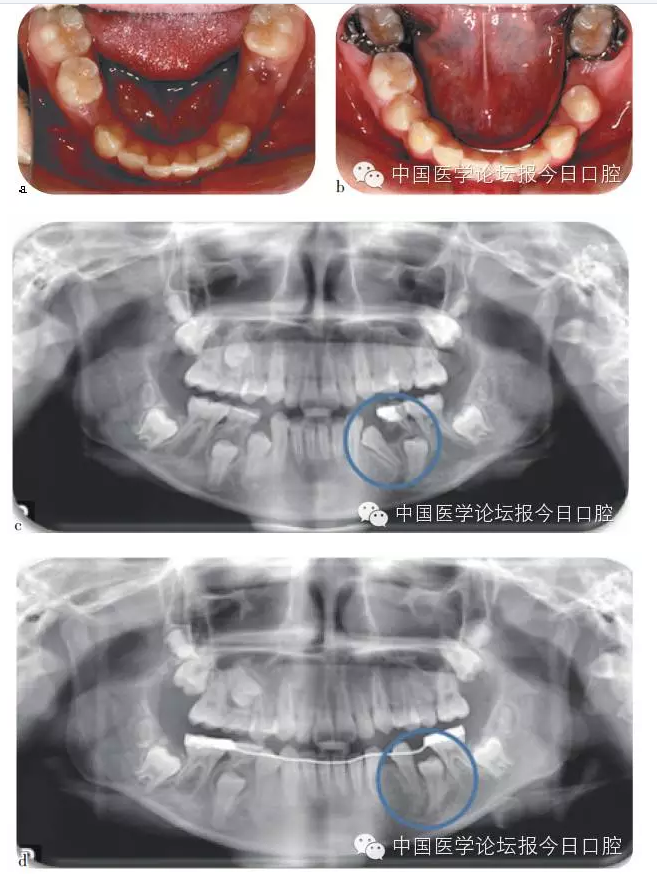

兒童齲病造成牙冠橫徑變短、乳牙早失、磨牙前移。兒童根尖周病影響恒牙發(fā)育及萌出異常、阻生。

兒童口腔疾病治療、間隙維持能預防繼承恒牙的萌出異常。

如病例一(圖1)所示,75深齲,34牙胚萌出異常,拔出75,行舌弓間隙維持后,34萌出道自行調(diào)整和萌出。

圖1 75深齲,34牙胚萌出異常,拔除75,舌弓間隙維持后,34萌出道自行調(diào)整萌出

錯牙合畸形截斷弓(“2×4”技術)治療

錯牙合在影響患兒咬合發(fā)育、口腔功能及口腔軟硬組織健康時,需要做早期矯治。“2×4”固定矯治技術可有效地矯治異位恒牙,避免錯對咬合發(fā)育的進一步影響,且效果較易保持。